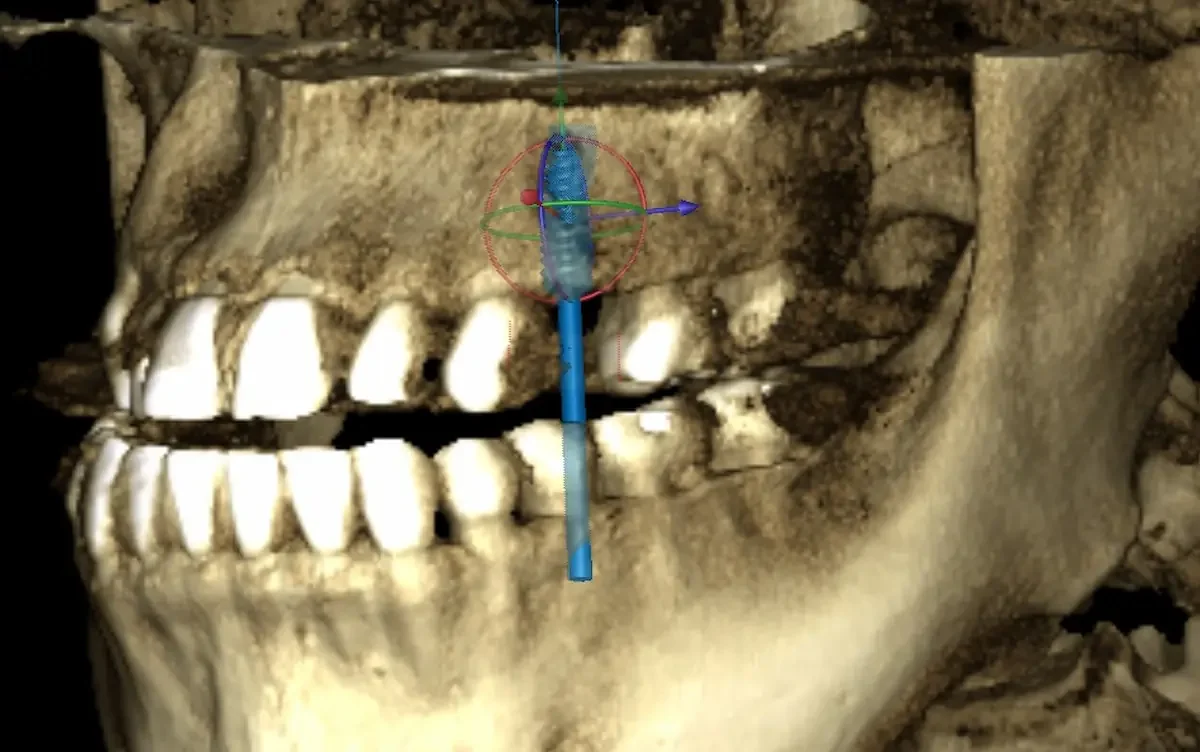

At Teuscher Legacy Dental, every implant case is planned with 3D cone beam CT imaging and digitally designed surgical guides — the same technology used by other leading surgical centers.

Visualize bone quality, and sinus anatomy, and nerve locations

Place implants with extreme precision

Often shorten healing time and improve comfort

Optimize location of future crown (the chewing part of the implant)

This first step also helps make sure the patient is on the same page with what to expect a final result to look like. We also go over financial details and timeline. This way the patient knows what to expect every step of the way!CBCT 3D Planning

CBCT (3‑D imaging) is used to assess bone quantity and quality and check for any sinus or nerve issues. There should be an evaluation of overall health (e.g., diabetes, smoking, medications) and other risk factors. Gum health should also be assessed (are there active gum infections?) and whether bone grafting is needed.Use of guided surgical planning

Digital planning and surgical guides help dentists place implants at the right angle, depth, and position, avoid critical anatomy (sinus, nerves), and preserve bone and soft tissue.Strict surgical protocol and sterile technique

Why it matters: The foundation of a successful implant starts with precision planning. During your consultation, our doctors use a cone-beam CT (CBCT) scan to create a 3D model of your teeth, bone, and jaw structure.

CBCT imaging allows us to measure bone density, identify vital structures (like nerves and sinuses), and plan the exact position of your future implant.

Using digital treatment planning, we design a custom surgical guide to ensure the implant is placed with millimeter accuracy.

3D scans (CBCT imaging) and digital planning lead to better fit, healing, and long-term success. A 2D X-Ray is less expensive, but also doesn’t allow for the same precision in planning where the implant post will sit in your jawbone. Sometimes, a dentist will use the 3D scan to generate a surgical guide, which allows for even greater precision when surgically placing the post.